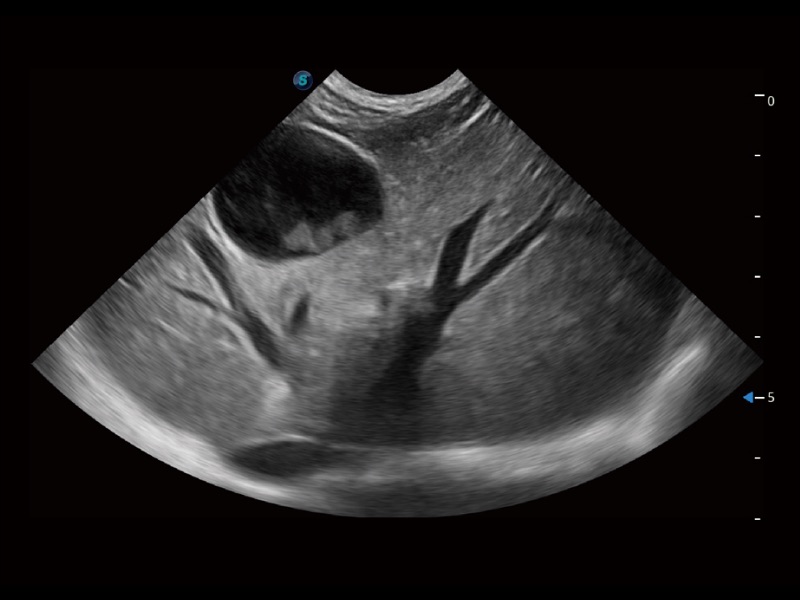

ProPet 70 進(jìn)一步提升了微米成像算法,更加注重對(duì)基礎(chǔ)原始圖像的還原和保留,在有效減少斑點(diǎn)噪聲、增強(qiáng)組織邊界顯示的同時(shí),避免過(guò)度優(yōu)化丟失真實(shí)的解剖信息。

ProPet 70專(zhuān)為動(dòng)物醫(yī)生設(shè)計(jì),對(duì)不同的動(dòng)物體型和生理結(jié)構(gòu)作出了針對(duì)性的優(yōu)化。通過(guò)動(dòng)物影像專(zhuān)用軟件,可滿(mǎn)足個(gè)性化的應(yīng)用需求,幫助動(dòng)物醫(yī)生獲得更精確的診斷數(shù)據(jù)。

ProPet 70 全新的動(dòng)物超聲智能軟件和豐富的探頭群,為動(dòng)物醫(yī)生提供了高清晰度和精細(xì)分辨率的圖像,無(wú)論在寵物、馬科、畜牧還是實(shí)驗(yàn)室動(dòng)物等應(yīng)用中都可以輕松應(yīng)對(duì),為您的日常工作帶來(lái)滿(mǎn)意的體驗(yàn)。